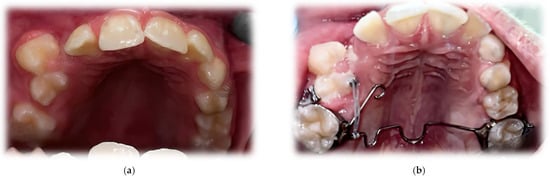

A functional assessment of the masticatory system did not reveal any kinematic jaw alteration. The movements of the mandible were symmetric, and their range was normal. Intraorally, mixed dentition was present with increased overjet and bilateral ½ cusp angle class II malocclusion. The oral vestibulum, in the area of the upper right primary canine (53) and first molar (54), was deformed due to alveolar bone expansion, and the overlying mucosa was red and swollen (Figure 2). The patient was referred for a radiological examination, as well as for a consultation at the Department of Oral Surgery.

Figure 2.

Intraoral photographs before treatment.

The initial orthodontic treatment plan required modification. Primarily, it was assumed that the traction of 13 would be required. This meant the need for the surgical exposure of the 13 crown, bonding of the attachment to the enamel surface and the application of an orthodontic fixed appliance in the upper dental arch. However, regular observations of 13 movement led to anticipating a spontaneous eruption on the condition that it would not be hindered by the malposition of Teeth 14 and 15. For this reason, the surgical exposure was unfounded. The aim of further orthodontic procedures was a distal movement of 14 and 15, to release the 13 eruption path. This was performed by an initial alignment with the aid of a specially designed transpalatal arch. On the right side, palatally from the first molar, an additional loop and a hook were added to a wire to enable the attachment of the elastic chain and provide a force to derotate the upper right second premolar (Figure 12). Subsequently, an attempt of derotation and alignment of the upper right first premolar was undertaken. However, due to the severe vestibuloposiotion of 14 and unfavorable alveolar boundary conditions, cautious orthodontic mechanics were required. Informed consent was obtained with notification of a possible revision in the treatment plan in case of a necessity to extract 14. The next step was a preadjusted fixed appliance therapy (MBT prescription, slot 0.022″) starting with a light continuous NiTi wire and continuing with a typical wire sequence and sliding mechanics (Figure 13).

Figure 12.

Upper occlusal photograph 9 months after surgery (a) and during orthodontic treatment (b).